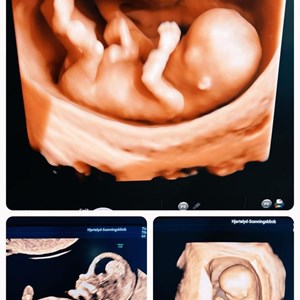

Når en 3D scanning bliver en magisk lille stund for den ventende familie 💞 Denne lille p...

Et spørgsmål jeg tit svarer på : ' Hvornår er det bedst at komme til 3D/4D scanning ?' �...